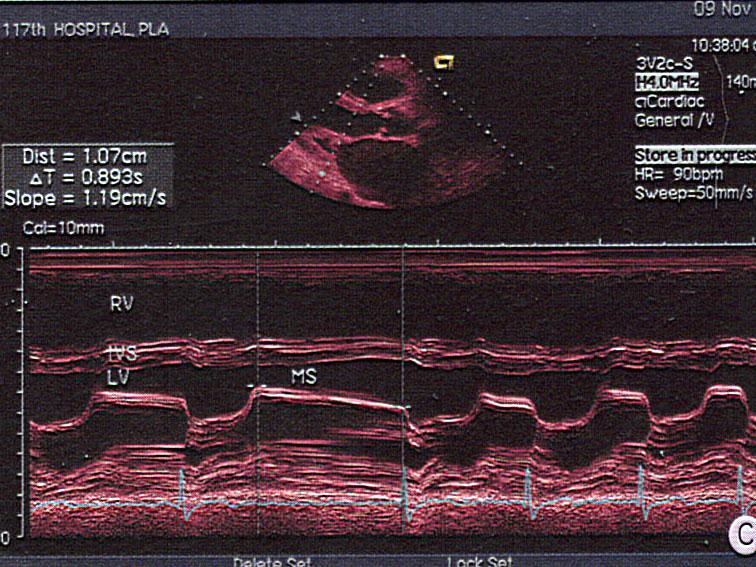

问题 该图所显示的病例为?(?)

选项 A.二尖瓣腱索断裂 B.二尖瓣脱垂 C.二尖瓣赘生物 D.风心二尖瓣狭窄 E.黏液瘤

答案 D